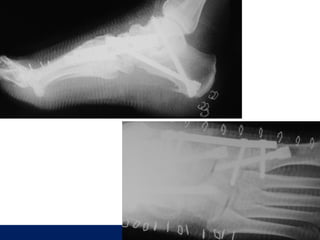

8 AY

ÖĞÜT